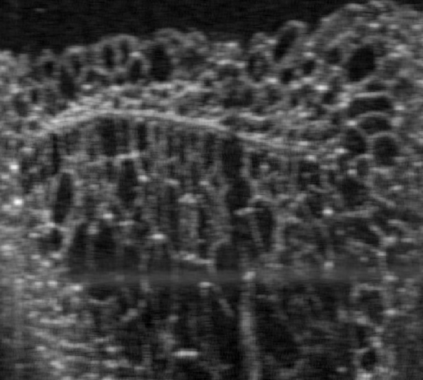

The statistical supervised learning framework assumes an input-output set with a joint probability distribution that is reliably represented by the training dataset. The learner is then required to output a prediction rule learned from the training dataset's input-output pairs. In this work, we provide meaningful insights into the asymptotic equipartition property (AEP) \citep{Shannon:1948} in the context of machine learning, and illuminate some of its potential ramifications for few-shot learning. We provide theoretical guarantees for reliable learning under the information-theoretic AEP, and for the generalization error with respect to the sample size. We then focus on a highly efficient recurrent neural net (RNN) framework and propose a reduced-entropy algorithm for few-shot learning. We also propose a mathematical intuition for the RNN as an approximation of a sparse coding solver. We verify the applicability, robustness, and computational efficiency of the proposed approach with image deblurring and optical coherence tomography (OCT) speckle suppression. Our experimental results demonstrate significant potential for improving learning models' sample efficiency, generalization, and time complexity, that can therefore be leveraged for practical real-time applications.